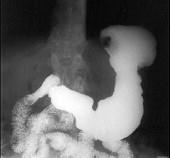

男,65岁,中上腹痛半年,X线检查如图,最可能的诊断是 ( )A.胃息肉B.胃溃疡C.胃浸润癌D.胃间质瘤E.糜烂性胃炎

问题 男,65岁,中上腹痛半年,X线检查如图,最可能的诊断是 ( )

选项 A.胃息肉 B.胃溃疡 C.胃浸润癌 D.胃间质瘤 E.糜烂性胃炎

答案 C